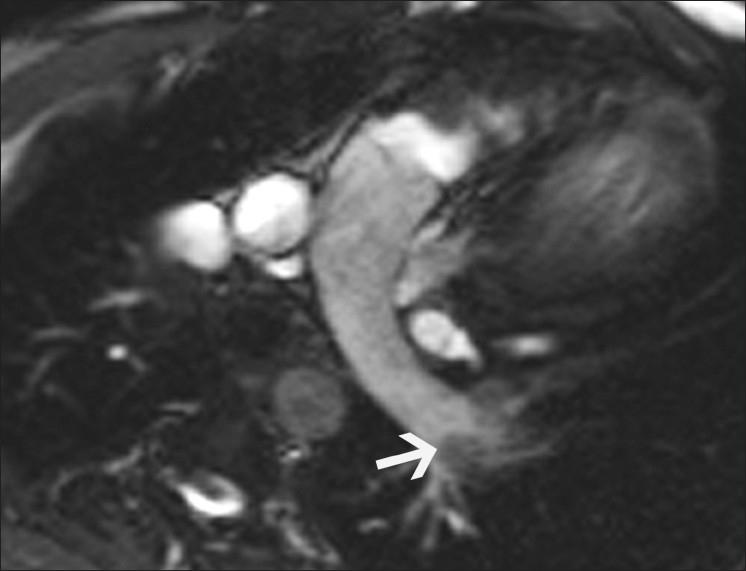

磁共振成像在评估心电图ST段抬高患者中的应用价值。

Utility of magnetic resonance imaging in the evaluation of patients with ST segment elevation on an electrocardiogram.

ST segment elevation is an important electrocardiographic (ECG) change that is typically found in acute myocardial infarction, but may also be seen in a variety of other conditions. MRI plays an important role in the evaluation of these patients. MRI not only establishes the diagnosis, which is essential for appropriate management, but also helps in the assessment of other factors that are important for risk stratification. In this review, we discuss the common and uncommon causes of ST segment elevation and the role of MRI in the evaluation of these disease processes.

摘要